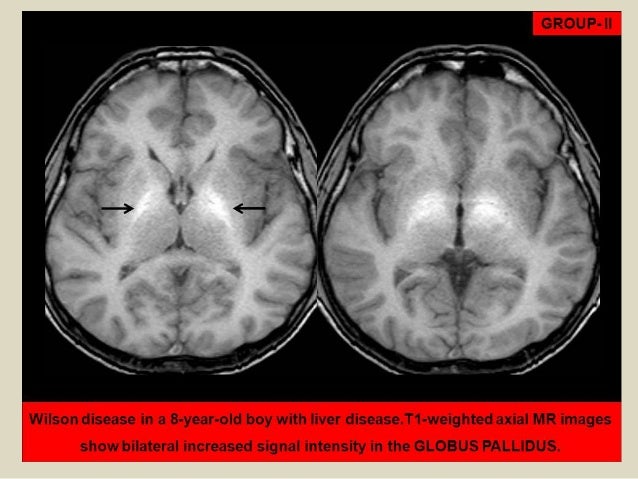

Classical Brain Mri Findings In Wilson S Disease Patients Bilateral Download Scientific Diagram

Figure 2 From Atypical Mri Features Of Wilson S Disease High Signal In Globus Pallidus On T1 Weighted Images Semantic Scholar

Figure 1 From Atypical Mri Features Of Wilson S Disease High Signal In Globus Pallidus On T1 Weighted Images Semantic Scholar